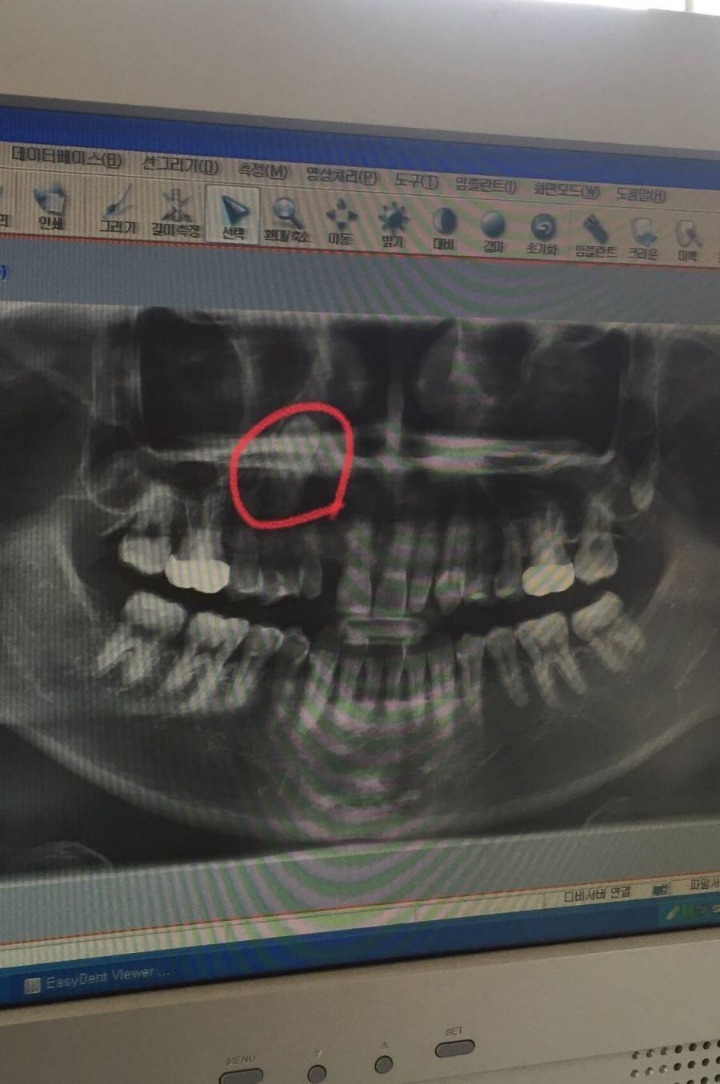

[스크랩] [흥미돋]치과의사도 포기한 치아

• 작성자오랑우탄보스 | 작성시간 25.10.30 나는 저거땜에 축농증생겨서 축농증수술했는데 안나아서 잇몸절개로 수술함 ㅜㅜ

• 작성자요즘 난 이래 | 작성시간 25.10.30 거길 왜 올라가있노ㅠㅠ

• 작성자저를아시나요 | 작성시간 25.10.30 나도 앞니 윗쪽잇몸에 이빨 두개 더있어...ㅎ근데 수술하면 잇몸다절개해서 빼내야된다고 안불편하면 그냥 살래서 그냥사는중임^^.....평생 함께하는거야 내 과잉치들아ㅠㅠ